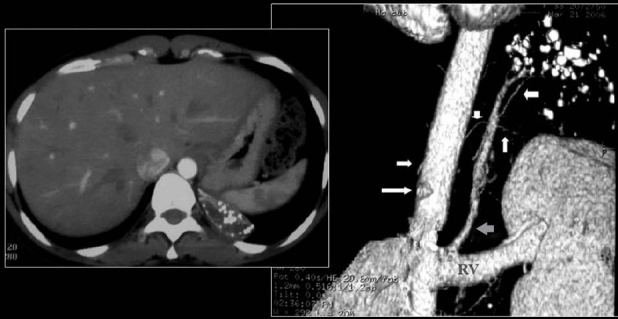

However, depending on their size and location, phleboliths can cause the following signs and symptoms: Mild pain in the area. What is a calcified tooth? Vascular calcifications are mineral deposits on the walls of your arteries and veins. Coronal CT shows chronic occlusion of the SVC with calcification.